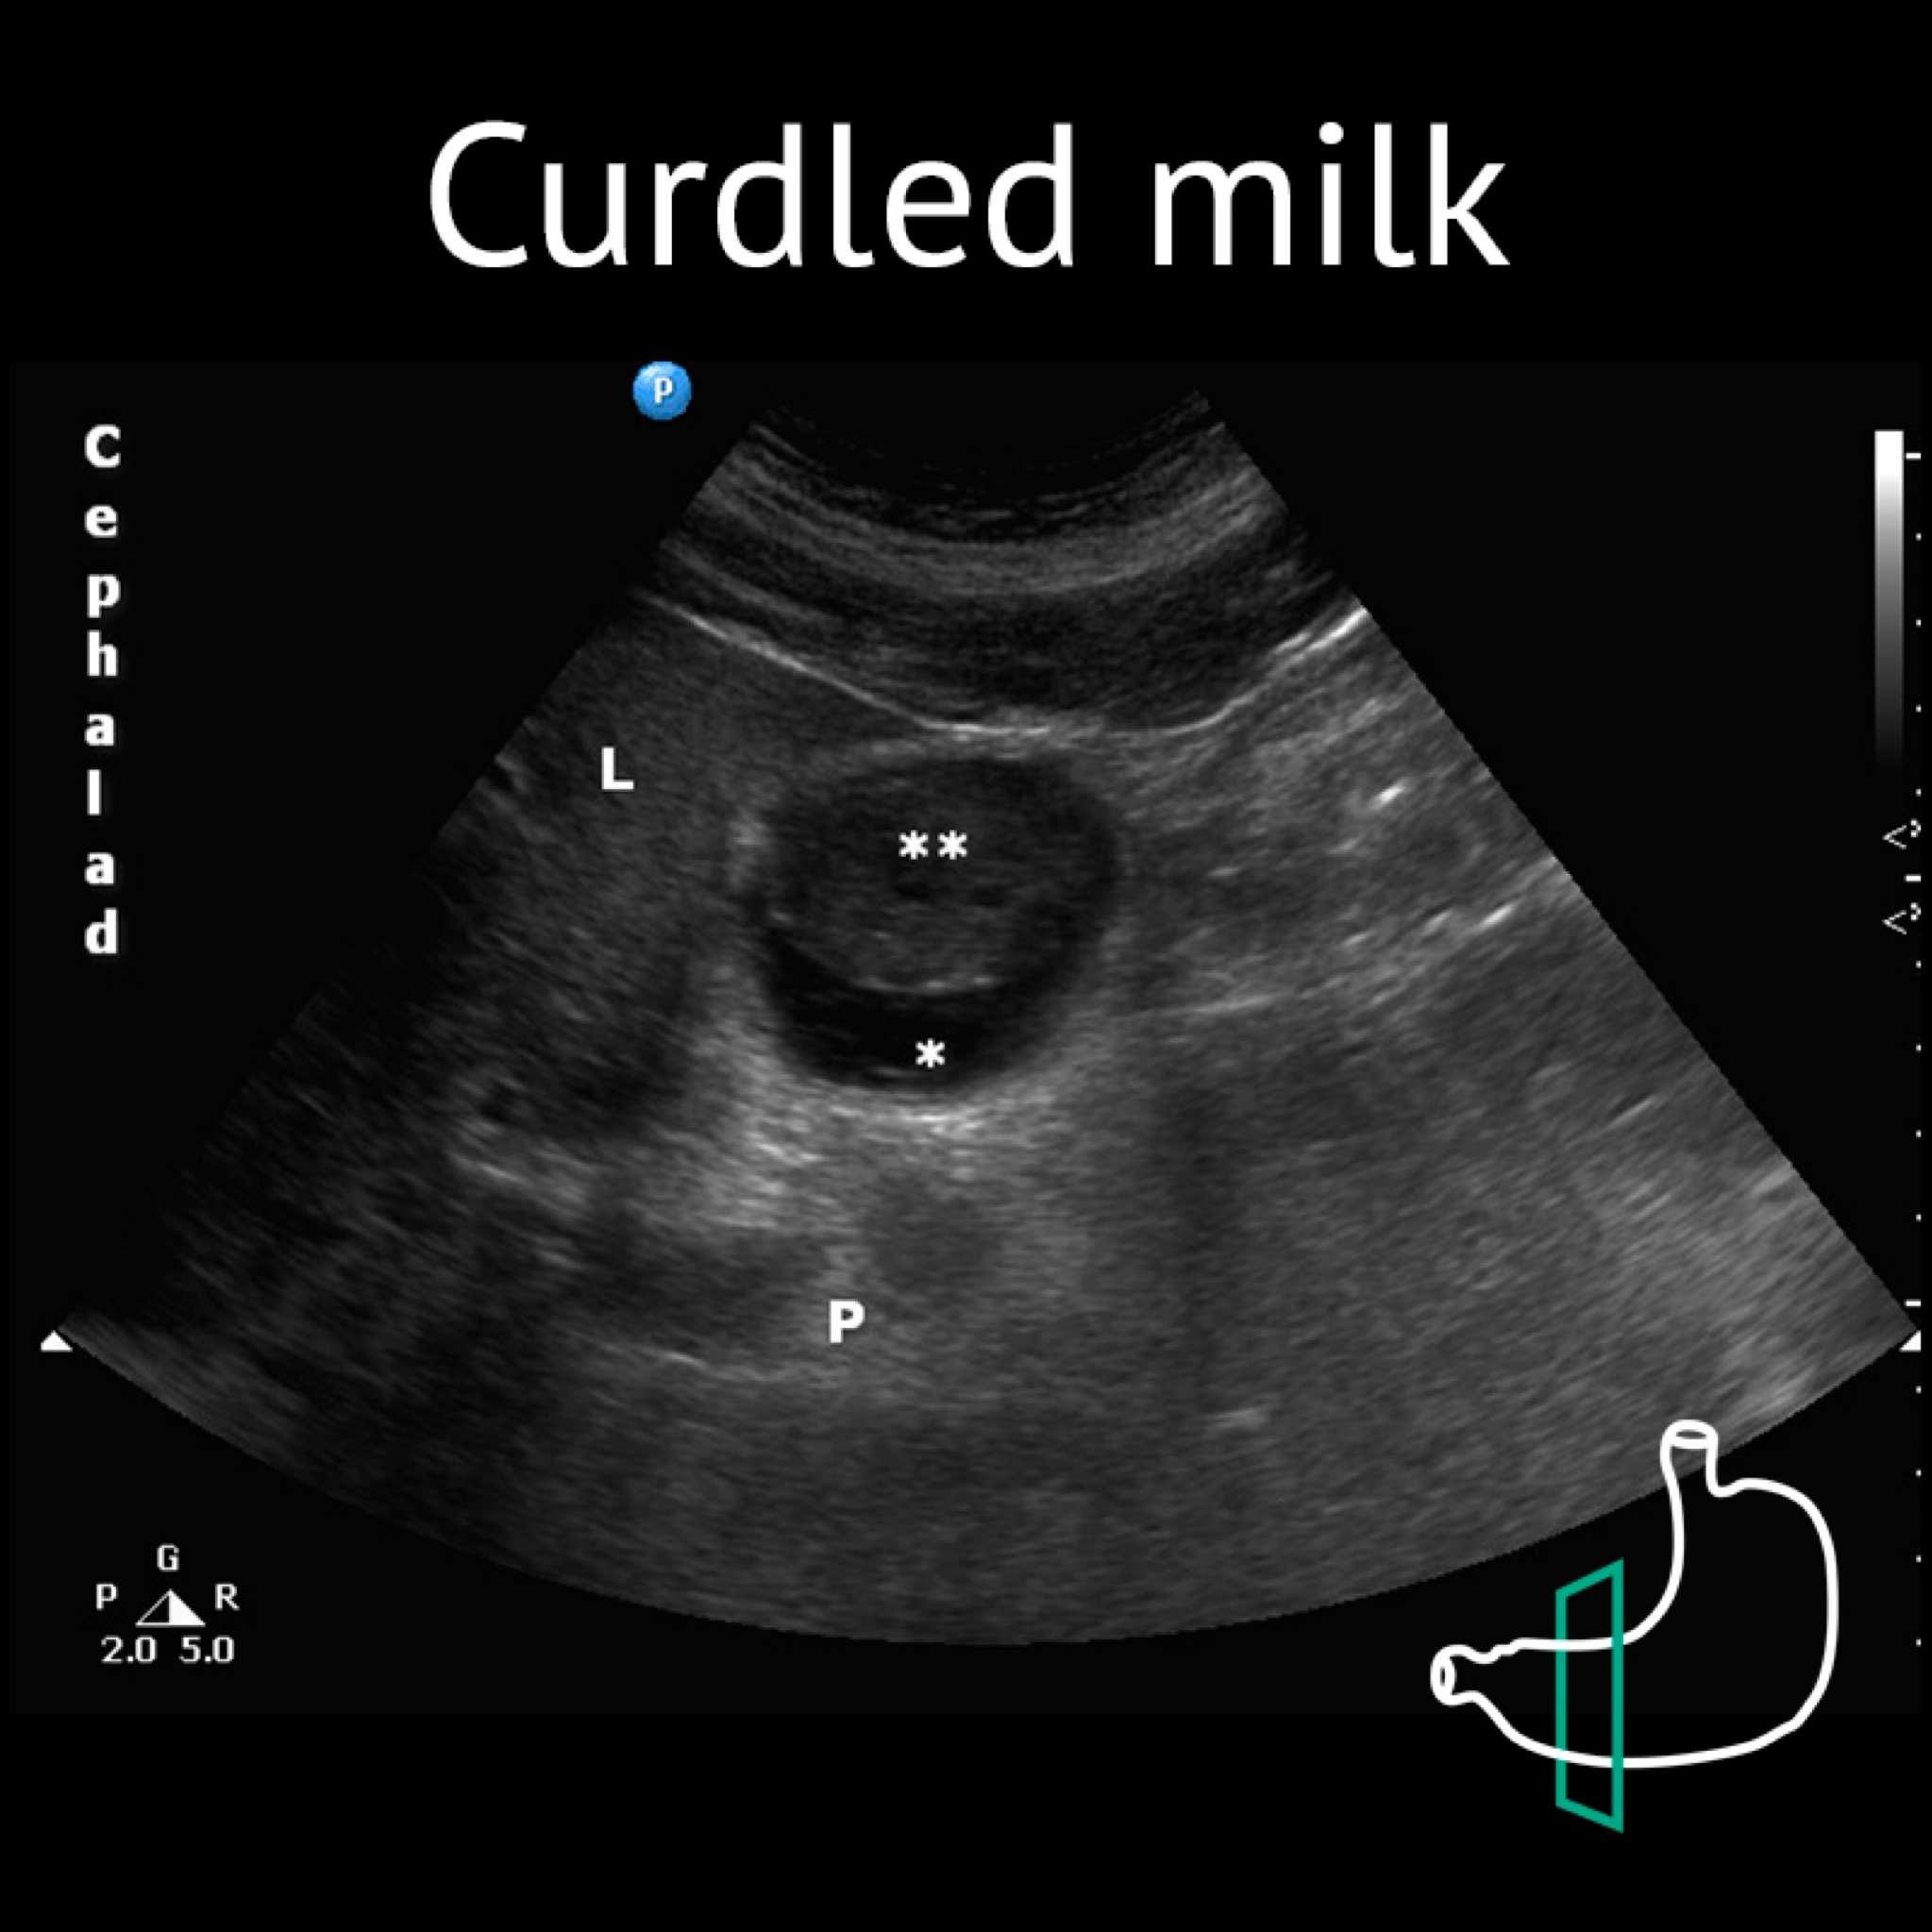

L: liver; P: pancreas; * clear fluid; ** curdled milk